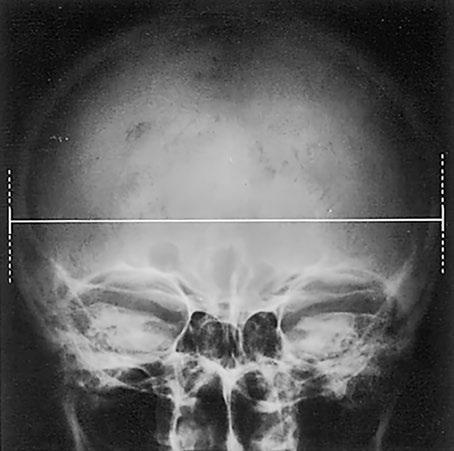

Lebka

Lebka ve dvou projekcích

Kalva je tvarem, tloušťkou a velikostí normální, mineralizace a struktura kosti jsou pravidelné Kontury kalvy se zobrazují hladké a ostré, bez patologických přerušení Zobrazení lebečních švů odpovídá věku Patologické kalcifikace nenalezeny

Báze lebeční anatomicky normálně konfigurovaná, hladce ohraničená s nenápadným zobrazením planum sphenoidale, tureckého sedla a zadní jámy lebeční Kontury v oblasti současně zobrazeného obličejového skeletu a horní krční páteře náležitě formované, hladké a ostře ohraničené Hodnotitelné paranazální dutiny nenápadné

Bez patologického nálezu v zobrazených měkkých tkáních

Závěr

Nenápadný nález na lebce

(obrázky viz str. 4)

Kontrolní seznam

Tvar, velikost – přibližně polokoule – rozměry (viz dále)

Tloušťka – normální tloušťka kostí (viz dále) – tři vrstvy (tabula interna, diploe, tabula externa)

Struktura – mineralizace – bez ohraničených ztluštění (ostrá/neostrá, rozmazaná, pruhovitá, skvrnitá) – ohraničené dekalcifikace, eroze (kruhovité, podélné, se sklerotizací?, linie fraktur?, ostré/neostré) – impressiones digitatae nezesílené, pravidelné

Cévní kanály – arterie, diploické žíly, emissaria: – průběh, tvar, tloušťka, kalibr, lokalizace

Kontury – lamina externa a interna hladké a ostré – bez přerušení kontinuity, bez schodovitých deformací – exostózy, apozice, spikula nejsou

Lebeční švy – průběh – otevřené/uzavřené (viz dále)

Intrakranium – kalcifikace? (pokud ano: lokalizace – např corpus pineale – ve střední čáře, bez dislokace)

Báze lebeční – konfigurace normální (viz dále) – přední, střední a zadní jáma lebeční – turecké sedlo není rozšířené

Obličejový skelet – frontální dutiny (poloha, pneumatizace) – dutina nosní (šířka, vzdušnost, přepážka nosní uprostřed)

– strop a stěny očnic intaktní

Krční páteř – postavení – dens axis (viz dále)

Měkké tkáně – krytí intaktní – bez otoku nebo cizích těles

Důležité rozměry a údaje

Rozměry lebky:

délka [d] + šířka [š] + výška [v] = 16,3–19,5 cm u mužů 3 15,7–19,5 cm u žen

Normální hodnoty: – délka 21,2 cm, šířka 16,8 cm, výška 15,6 cm u mužů – délka 20,1 cm, šířka 16,2 cm, výška 15,1 cm u žen

(1) Tloušťka kosti lebeční kalvy:

(a) tabula interna: asi 0,5 mm

(b) tabula externa: asi 1,5 mm

(2) Kortikalis: frontálně celkem asi 5 mm (orientační hodnoty jsou jen přibližné kvůli výrazné interindividuální a intraindividuální variabilitě, nejtenčí místa jsou např strop očnice, šupina kosti spánkové, jamka čelistního kloubu; nejsilnější místo je tuber parietale, 3–8 mm)

Lebeční švy: od 20 roku všechny uzavřené, šev čelní jako jeden z prv

ních již před 3 rokem, kdežto synchondrosis sphenooccipitalis zůstává otevřená až do 20 roku, osifikovaná od 40 roku

Báze lebeční:

(3) úhel báze lebeční (nasion – tuberculum sellae – basion) = 123–152°

(4) Boogardův úhel (foramen magnum – klivus) = 119–135°

(5) postavení krční páteře k bázi lebeční: konec dens axis nepřesahuje palatookcipitální linii (p) o více než 5 mm